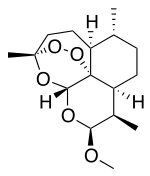

| Formula | C16H26O5 |

| 3D model (JSmol) | |

Artemether is a methyl ether derivative of artemisinin, which is a peroxide-containing lactone isolated from the antimalarial plant Artemisia annua. It is also known as dihydroartemisinin methyl ether, but its correct chemical nomenclature is (+)-(3α,5aβ,6β,8aβ,9α,12β,12aR)-decahydro-10-methoxy-3,6,9-trimethyl-3,12-epoxy-12H-pyrano[4,3-j]-1,2-benzodioxepine. It is a relatively lipophilic and unstable drug,[20] which acts by creating reactive free radicals in addition to affecting the membrane transport system of the plasmodium organism.[13]